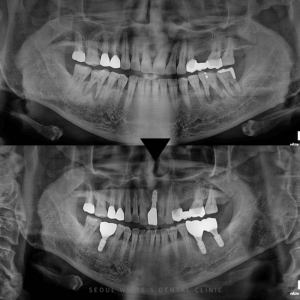

영도치과, 발치 후 즉시 임플란트 식립 사례 안녕하세요 영도치과 서울화이트S치과입니다. 저희 치과에는일과 병행하며 내원하시는 직장인 환자분들이 많습니다. 그만큼 진료 과정에서 불필요한 절차를 줄이고 꼭 필요한 부분만 집중하는 것이…